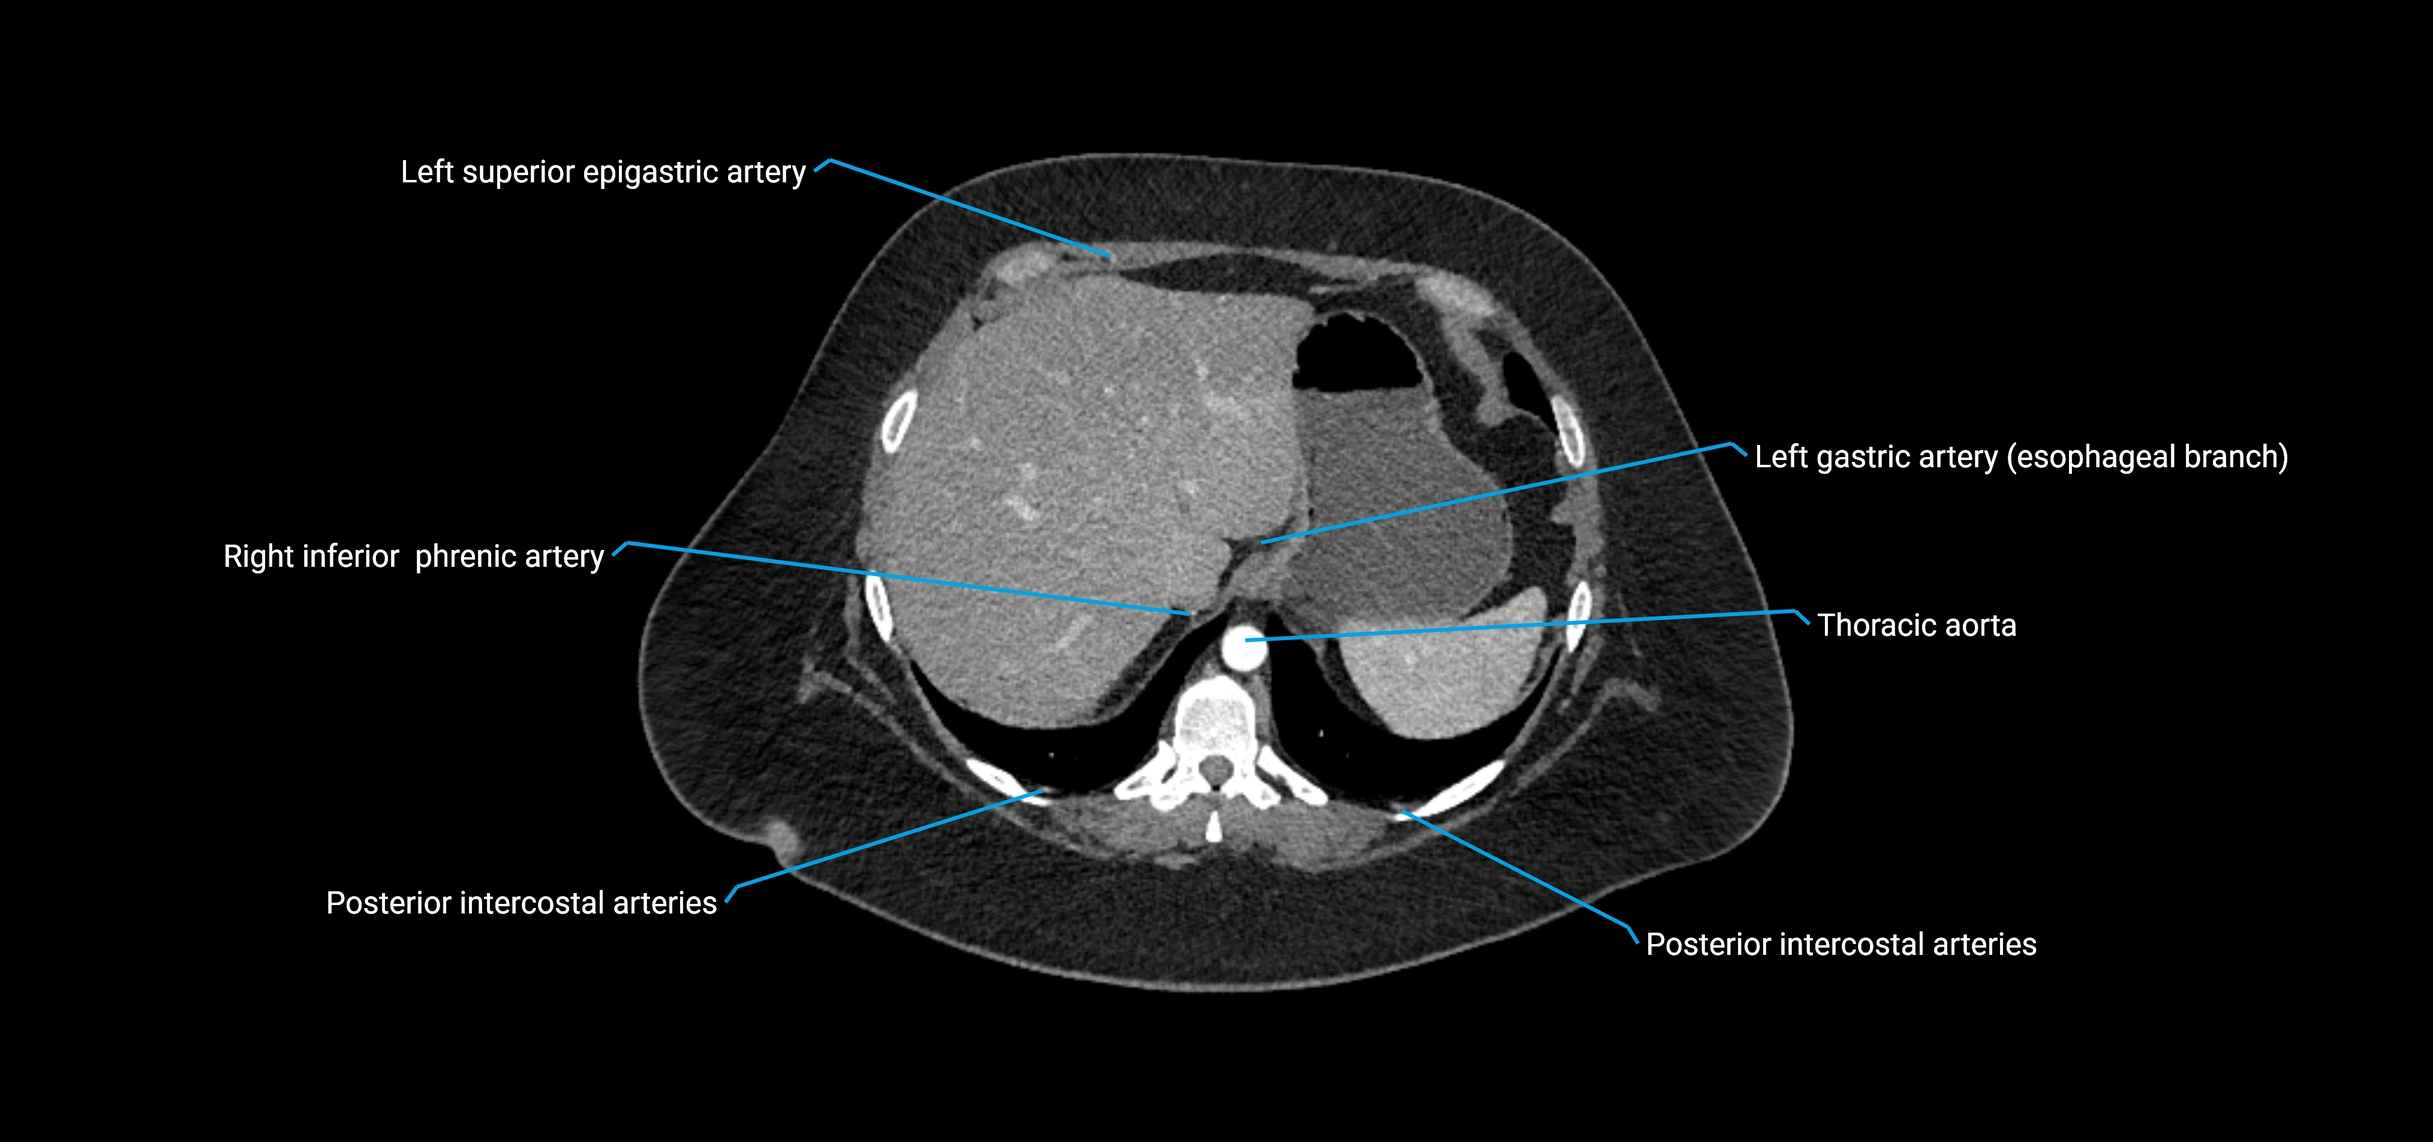

CT images

image

Contrast-enhanced CT (CTA):

• Gold standard for abdominal aortic imaging

• Provides excellent detail of lumen, wall, aneurysm, thrombus, and branch vessels

• Multiplanar and 3D reconstructions help in aneurysm measurement, stent graft planning, and dissection evaluation